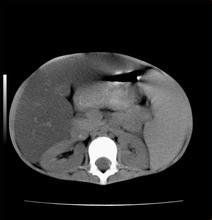

肝脂肪浸潤指的是肝內的部分區域有脂肪成分,類似於局灶性的脂肪肝。而脂肪肝一般是瀰漫性全肝都有的情況。也就是說,比起典型的脂肪肝來,肝脂肪浸潤的肝臟脂肪化程度輕一些,範圍小一些。通過控制飲酒、調節飲食、積極鍛鍊的方法可以恢復肝健康。

肝臟內的脂肪含量增多,脂肪細胞大量充盈於肝細胞內,稱肝脂肪浸潤。所謂脂肪肝,是指肝脂肪過量浸潤,肝內脂肪含量超過肝臟重量的10%,或組織學上80%以上的肝實質脂肪化的一種病態